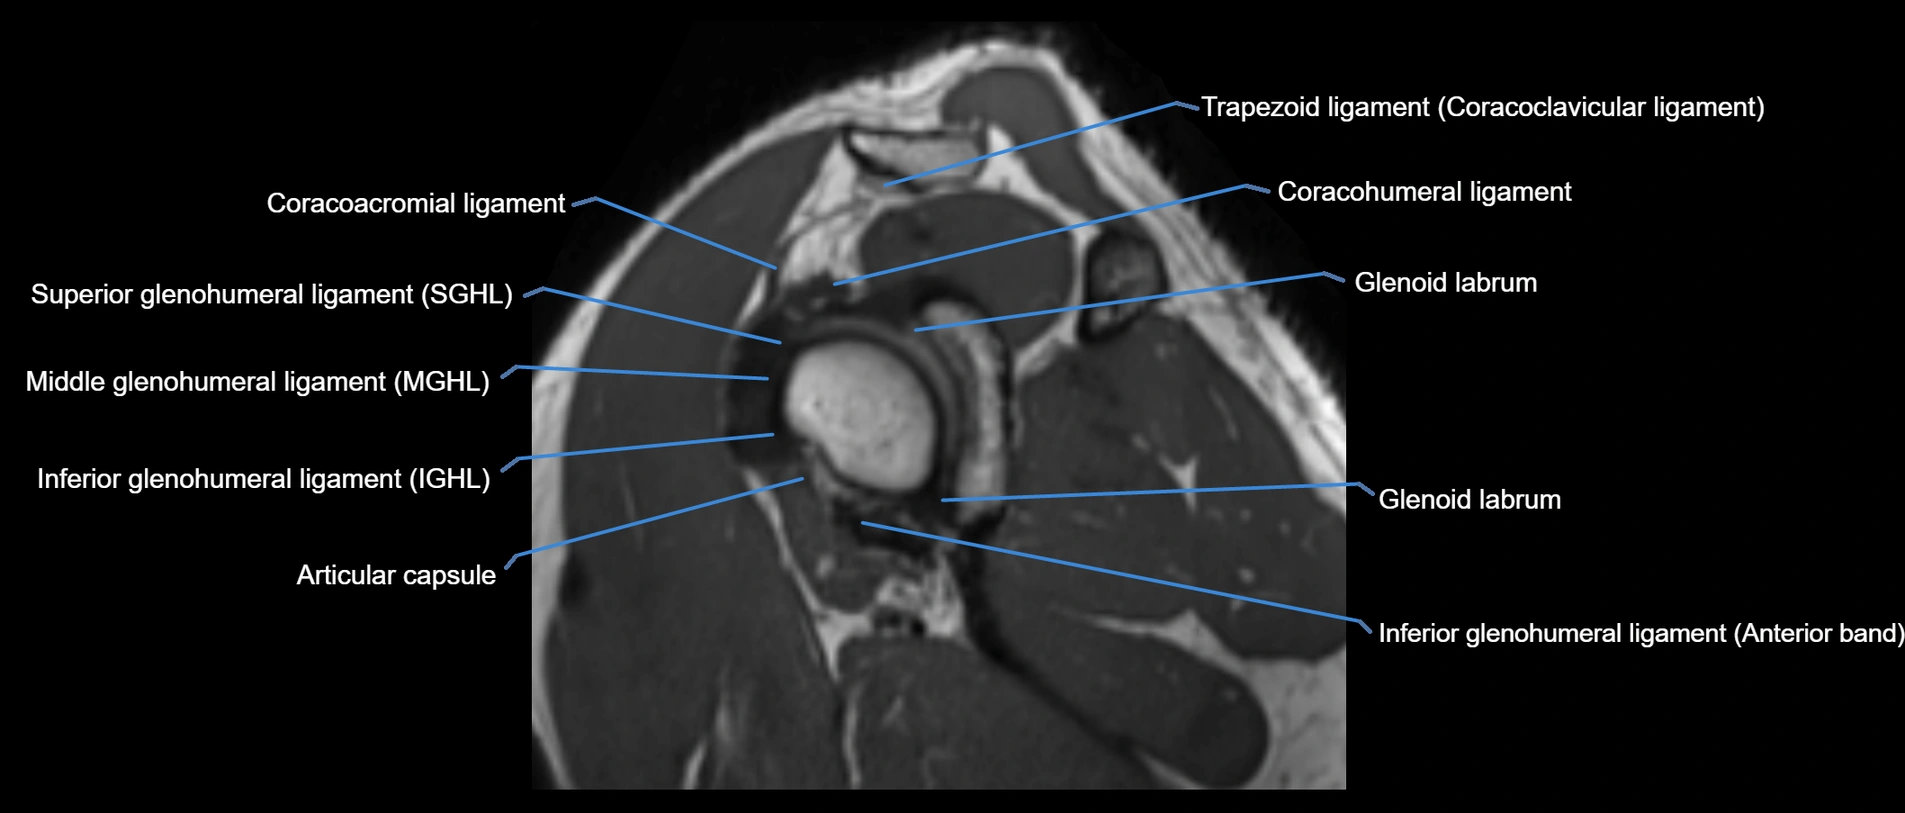

MRI images

image